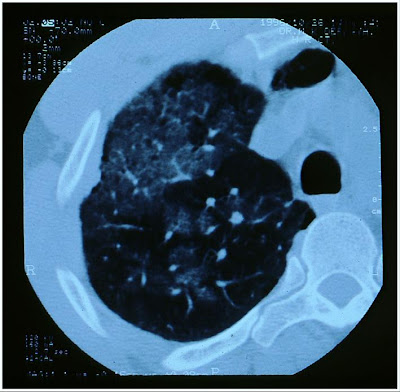

Atlas of medicine is a useful resource that brings together various pearls of medical wisdom and aims to bridge the gap between clinical theory and practice .This well organized site contains a good collection of clinical images, and X-rays, CT scan, clinical examination and procedure images, making this a feature rich site with a strong focus on clinical learning.